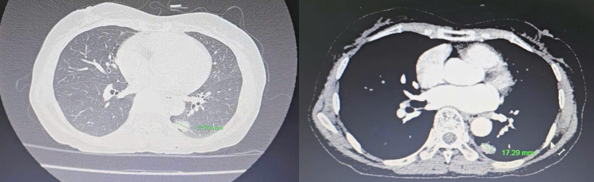

- Cắt lớp vi tính lồng ngực: hình ảnh nốt đặc thùy dưới phổi trái kích thước 13x16mm, ngấm thuốc mạnh sau tiêm, bờ tua gai. Hạch trung thất không to.

Do tổn thương u phổi đơn độc, đặc điểm hình ảnh định hướng đến tổn thương nguyên phát hơn là di căn, đồng thời, khối u dạ dày ở giai đoạn sớm (cT2) chưa di căn hạch, nên bệnh nhân được chẩn đoán sơ bộ đây là một trường hợp ung thư đồng thời ở giai đoạn sớm hơn là ung thư dạ dày di căn phổi hay ngược lại. Do đó bệnh nhân đã được quyết định làm sinh thiết tổn thương phổi.